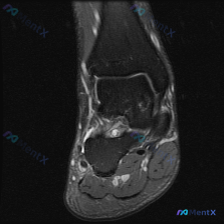

病例影像分析分享 今天整理了一例踝关节MRI的分析思路,原始提示看到「软组织积液」,我们一步步来拆解: 病例影像基本信息 这是一例踝关节MRI冠状位T2加权像,我们先做系统性解剖评估: 1. 骨与关节:胫距关节、距下关节间隙正常,关节面平滑,胫骨远端、距骨、跟骨骨髓信号均匀,没有骨赘、软骨下囊肿、骨...